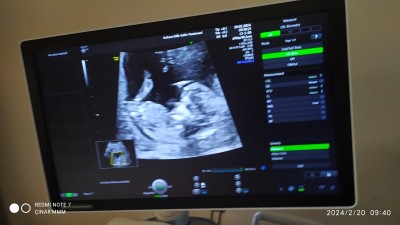

Cinsiyetten alayan varmı acaba ne dir sizce kızlarr

Gebelik haftası 16 haftada